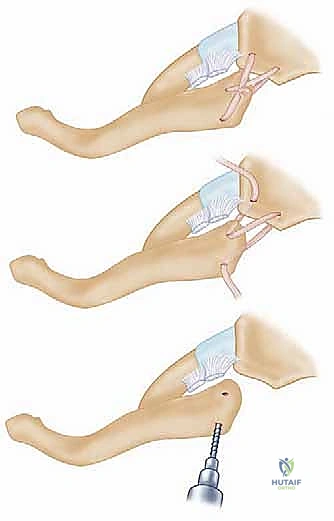

لا يمكن ببساطة خياطة الأربطة الممزقة لضمان الاستقرار. لذلك، يستخدم الدكتور هطيف تقنية متقدمة لإعادة البناء باستخدام "رقعة وترية" (Tendon Graft).

* أخذ الرقعة: غالباً ما تؤخذ من وتر العضلة الرشيقة (Gracilis) أو العضلة نصف الوترية (Semitendinosus) من ركبة المريض نفسه (Autograft)، أو استخدام رقعة صناعية طبية عالية الجودة.

* حفر الأنفاق العظمية: يتم حفر ثقوب دقيقة جداً في عظم الترقوة وعظم القص باستخدام أدوات جراحية متطورة.

5. تمرير الرقعة وتثبيتها (تقنية الرقم 8)

يتم تمرير الرقعة الوترية عبر الثقوب العظمية بنمط يشبه الرقم 8 (Figure-of-eight). هذه التقنية الميكانيكية الحيوية توفر قوة استقرار هائلة تحاكي قوة الأربطة الطبيعية (الرباط الكبسولي والرباط الضلعي الترقوي).

تحذير طبي هام: في الماضي، كان بعض الجراحين يستخدمون أسياخ معدنية (K-wires) لتثبيت المفصل. الأستاذ الدكتور محمد هطيف يمنع تماماً استخدام هذه الأسياخ في هذا المفصل، حيث أثبتت الدراسات الطبية أن هذه الأسياخ قد تهاجر وتخترق القلب أو الرئتين مسببة الوفاة. بدلاً من ذلك، يعتمد الدكتور هطيف على خيوط جراحية فائقة القوة (Suture anchors) والرقع الوترية الطبيعية التي تندمج مع الجسم.